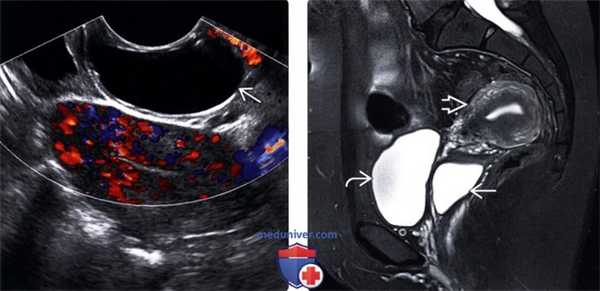

(Слева) При ТВУЗИ в продольной плоскости с применением ЦДК в стенке влагалища выявляется гипоэхогенное аваскулярное объемное образование. Наличие феномена акустического усиления задней стенки подтверждает кистозный характер объемного образования.

(Справа) При МРТ на Т2-ВИ в аксиальной плоскости у той же пациентки в переднебоковой стенке влагалища определяется гиперинтенсивная киста с четкими границами и гомогенной структурой. Визуализируется окаймляющий кисту бледный гипоинтенсивный ободок, который обусловлен отложением ге-мосидерина после ранее произошедшего кровоизлияния.